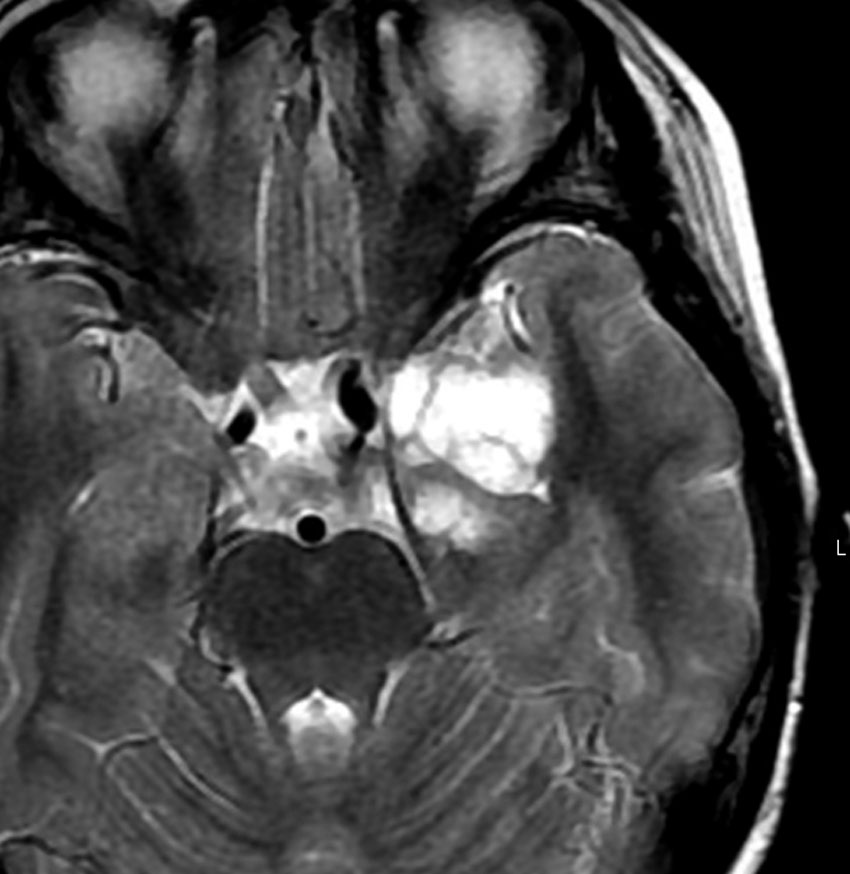

35歳,側頭葉てんかんで発症した右側頭葉の乏突起膠腫 グレード2です。全摘出して化学療法4コースと54グレイの局所放射線治療 generous local fieldを行いました。7年後に同じ部位に再発して摘出したところ退形成性乏突起膠腫 グレード3となっていました。手術摘出して,テモゾロマイド化学療法で維持療法をしていました。

その2年後の画像です。右小脳半球に再発しています。右側頭葉腫瘍との連続性は全くありませんでした。脳幹部にも腫瘍はありません。遠隔再発 remote recurrenceというもので,星細胞系腫瘍 astroytic tumor AAやGBMではよく知られている現象です。乏突起膠細胞系腫瘍でもまれにみられます。